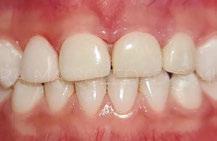

Several clinical solutions exist for primary anterior teeth with multisurface decay. Full coronal restoration of carious primary incisors may be indicated when caries is present on multiple surfaces, pulpal therapy is indicated, caries may be minor, but oral hygiene is very poor, or in a child with severe early childhood caries or a high caries risk diagnosis.1 Depending on the clinical scenario, a minimally invasive approach with the utilization of a high viscosity glass ionomer cement (HVGIC), with or without the combination of silver diamine fluoride (SDF) in a strip crown form, may pause the caries progression and provide an adequate clinical solution. Resin composite strip crowns have shown 80% retention rates and adequate parental satisfaction,1-4 although composite resin strip crowns have shown lower retention rates in teeth with decay involving three or more surfaces and particularly in children with a high caries risk4-6 (Figure 1). This could be from the continued high caries risk behaviors of the patient, as composite resin strip crowns in this population have shown to have increased inflamed marginal gingiva and gingival bleeding, increased plaque retention along the restoration, and loss of some restorative material.5,6

2: NuSmile® Anterior Zirconia crowns at 2-year follow up. Note the high amount of plaque accumulations along the untreated cuspid and existing stainless-steel crowns

Figure 1: Occlusal films at recall visit in high caries risk patients showing loss of material and recurrent decay in composite resin strip crowns Figure